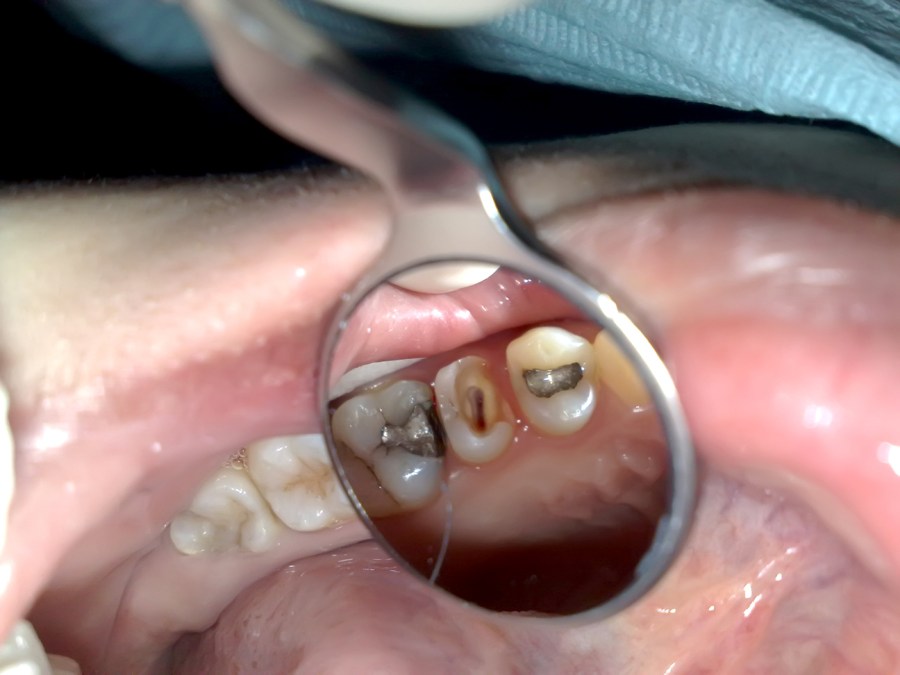

Endodontic treatment of upper left first premolar with remaining buccal wall

Endodontic treatment on lower right first molar with radix entomolaris

Endodontic treatment on upper left first molar with broken mesial and distal wall